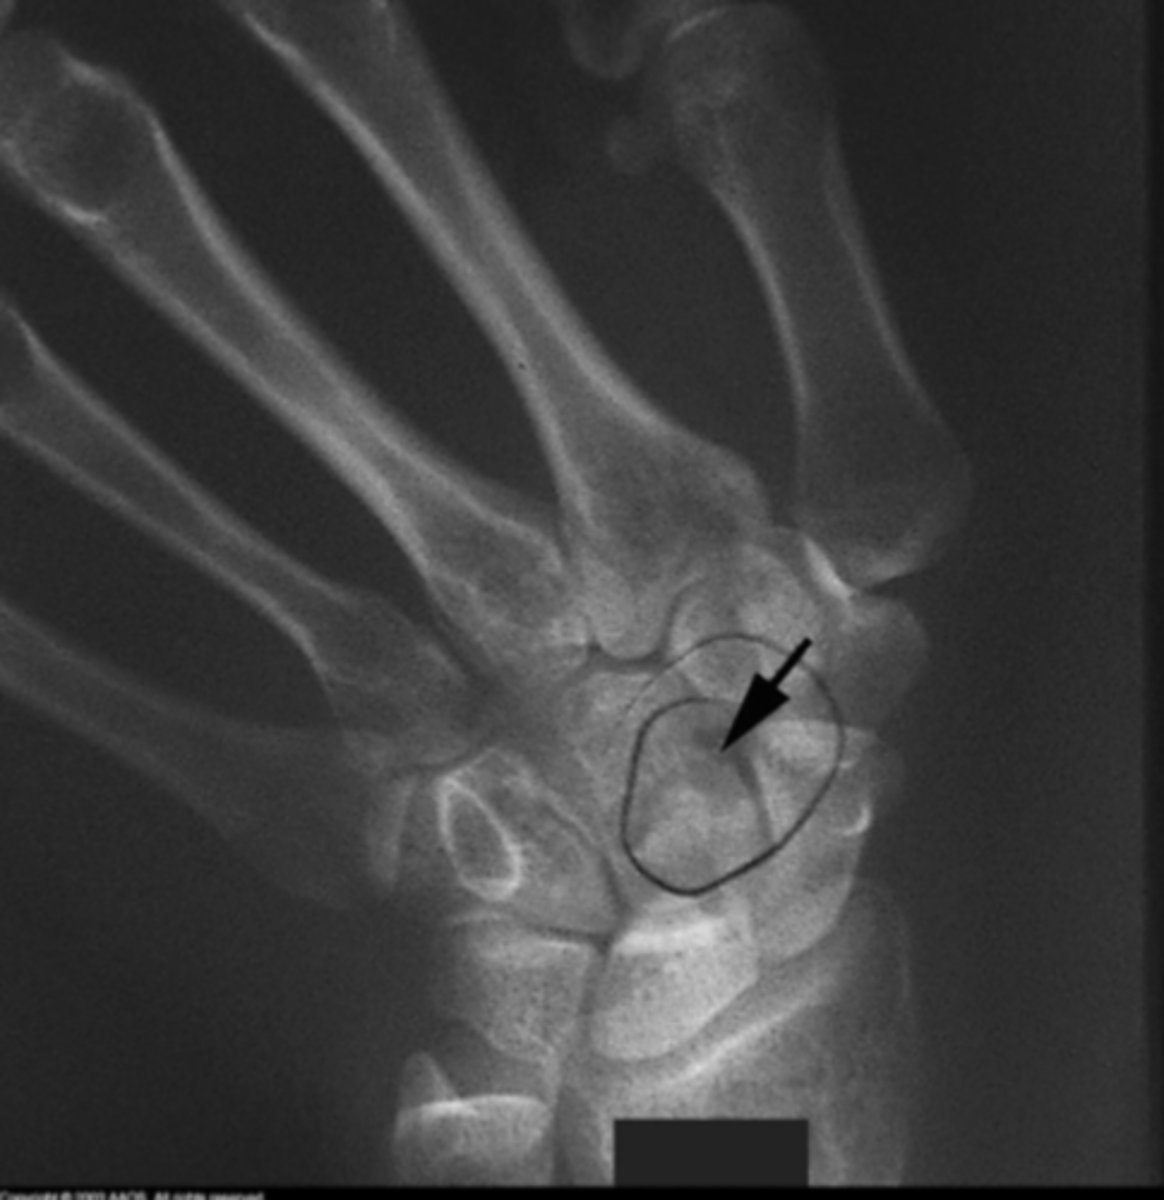

Ganglion cyst

What is the issue?

TFCC disorder